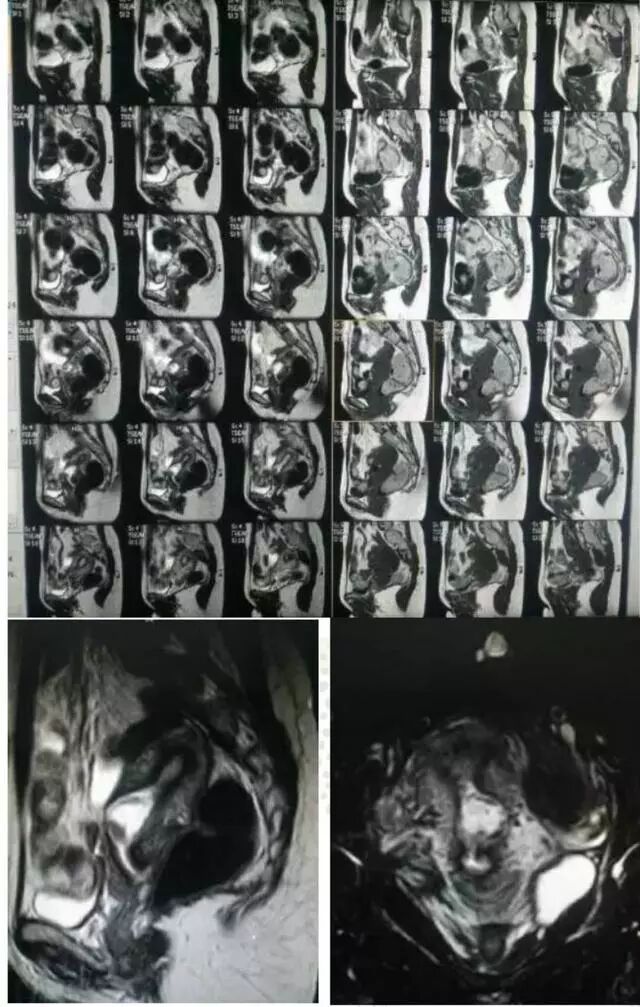

妇产科医护团队

术前影像图片

2.如何早期诊断剖宫产后子宫疤痕妊娠? 剖宫产瘢痕妊娠可导致子宫破裂、大出血,危及患者的生命,早期诊断尤为关键。诊断应依赖病史、临床表现包括停经史、腹痛、阴道出血等。影像学技术包括阴道彩超、三维B超、MRI。阴道彩超认为是诊断剖宫产瘢痕妊娠最基本的检查技术,文献报道其敏感度为84.6%。三维B超可识别与妊娠相关的新生血管形成特征,特别有助于评估子宫动脉栓塞术的治疗效果。对超声诊断有怀疑的病例,专家建议加用MRI帮助确定诊断,MRI图像可清楚地显示孕囊在子宫前壁着床位置。